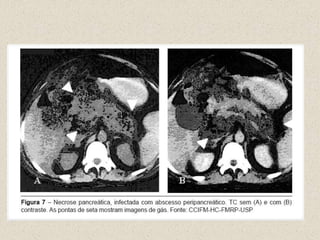

TOMOGRAFIAMelhor exame de imagem para diagnosticar as lesões pancreáticasEstratificar a doençaDiagnosticar complicaçõesOrientar punções aspirações , intervenção cirúrgicaIndicada após 48H sem melhoraContraste EVEdema ,necrose,abscesso , complicações

TOMOGRAFIAQuando indicar TC com contraste iodado:Casos com diagnóstico clínico duvidosoPacientes com hiperamilasemia , e PA grave, distensão abdominal,febre alta leucocitoseÍndice de Rason maior que 3 ou APACHE II maior ou igual a 8Casos que não apresentam melhora rápida nas primeiras 72 horas com tratamento conservadorPacientes que apresentam uma melhora inicial e posteriormente tem mudança abrupta do quadro com piora clínica

Fig 1 : Necrose pancreáticaFig 2: Pseudocisto pancreáticoFig 3: Abscessos pancreáticos

Fig 1 :Necrose pancreáticaFig 2: Pseudocisto pancreáticoFig 3: Abscessos pancreáticos